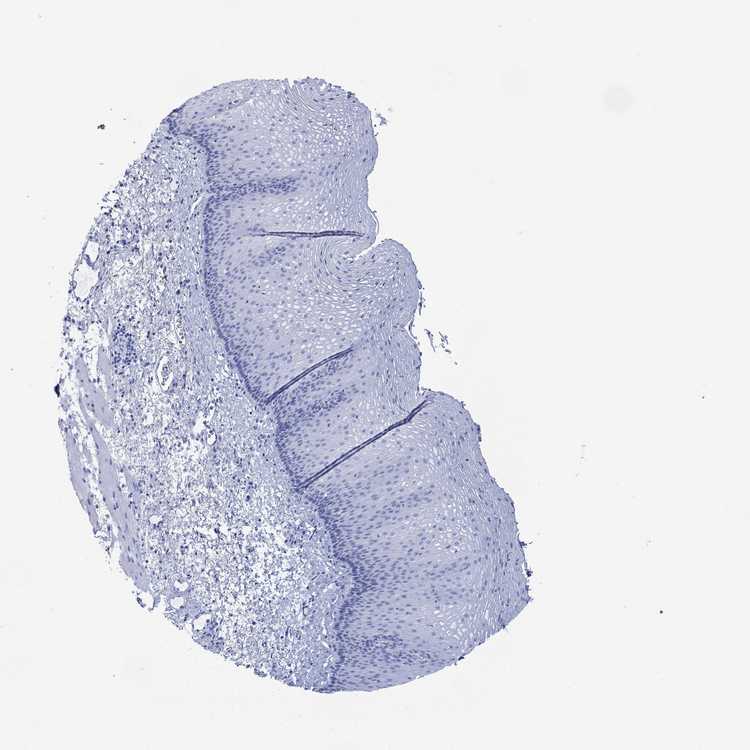

ESOPHAGUS - Antibody stainingi

Antibody staining in the annotated cell types in the current human tissue is reported as not detected, low, medium, or high, based on conventional immunohistochemistry profiling in selected tissues. This score is based on the combination of the staining intensity and fraction of stained cells.

Each image is clickable and will lead to virtual microscopy that enables deeper exploration of all samples and also displays staining intensity scores, fraction scores and subcellular localization as well as patient and tissue information for each sample.

Antibody HPA037986

Squamous epithelial cells Not detected